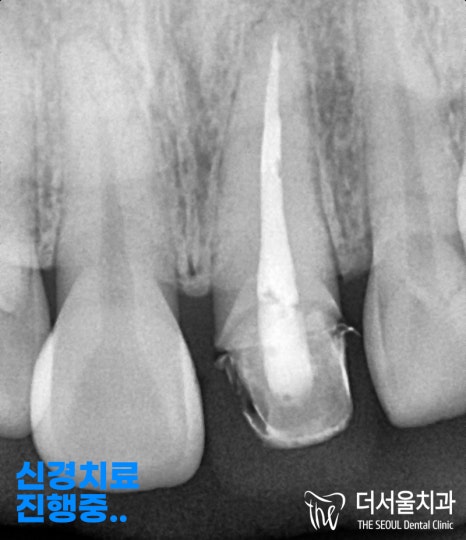

『근관치료 진행중…』

죽어버린 치수 조직을 제거하며,

충전 재료로 빈 공간을 채워드리는

과정을 진행합니다.

그 뒤에 크라운 보철을 씌울 수 있도록

프렙(Prep)이라는 단계를 시행합니다.

그 뒤에 프렙으로 모형을 다듬어

본을 뜬 뒤에 크라운을 세팅하여

오래 사용할 수 있도록 해줍니다.